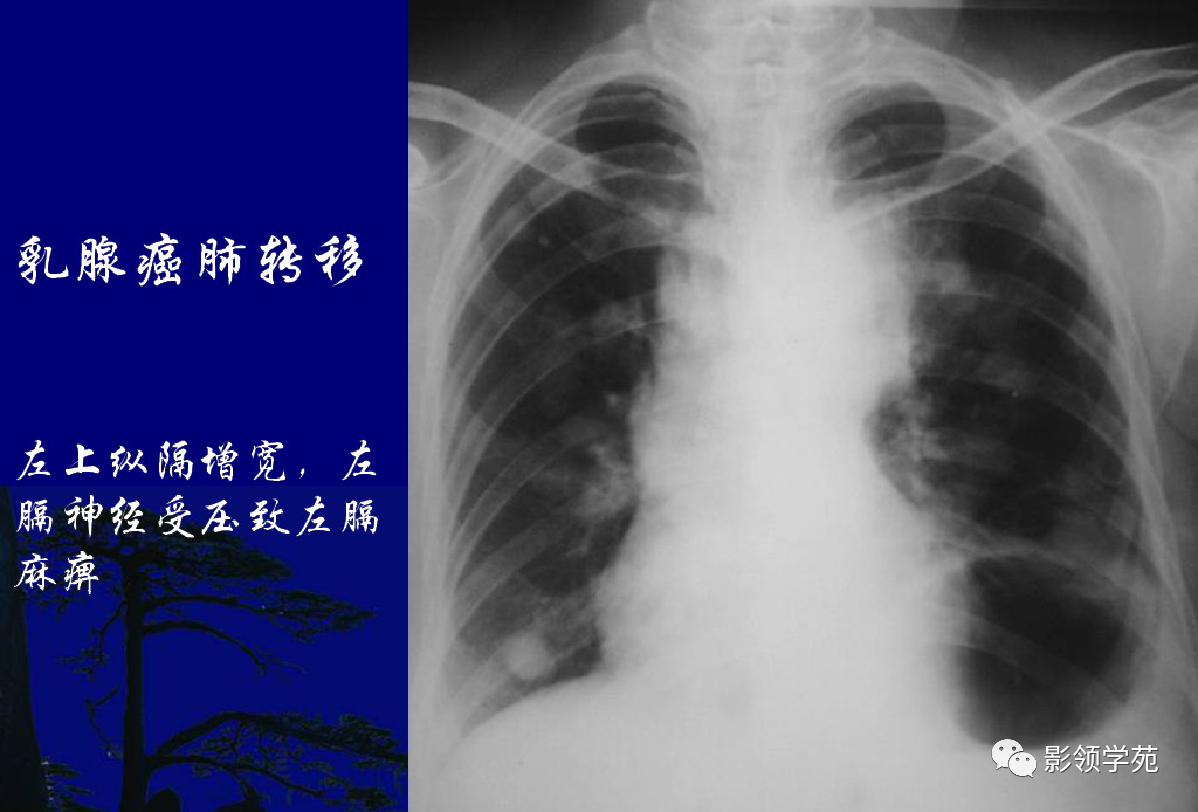

淋巴转移:肺门影增大,自肺门向外部规则索条状影(下图)

瘤外科患者,女,48岁,左乳癌根治术后2月术后化疗。病理:左乳伴髓样癌特征的乳腺浸润性导管癌。术后TAC方案化疗1个周期。

左乳切除术后,左肺下野两个大小不等高密度影。